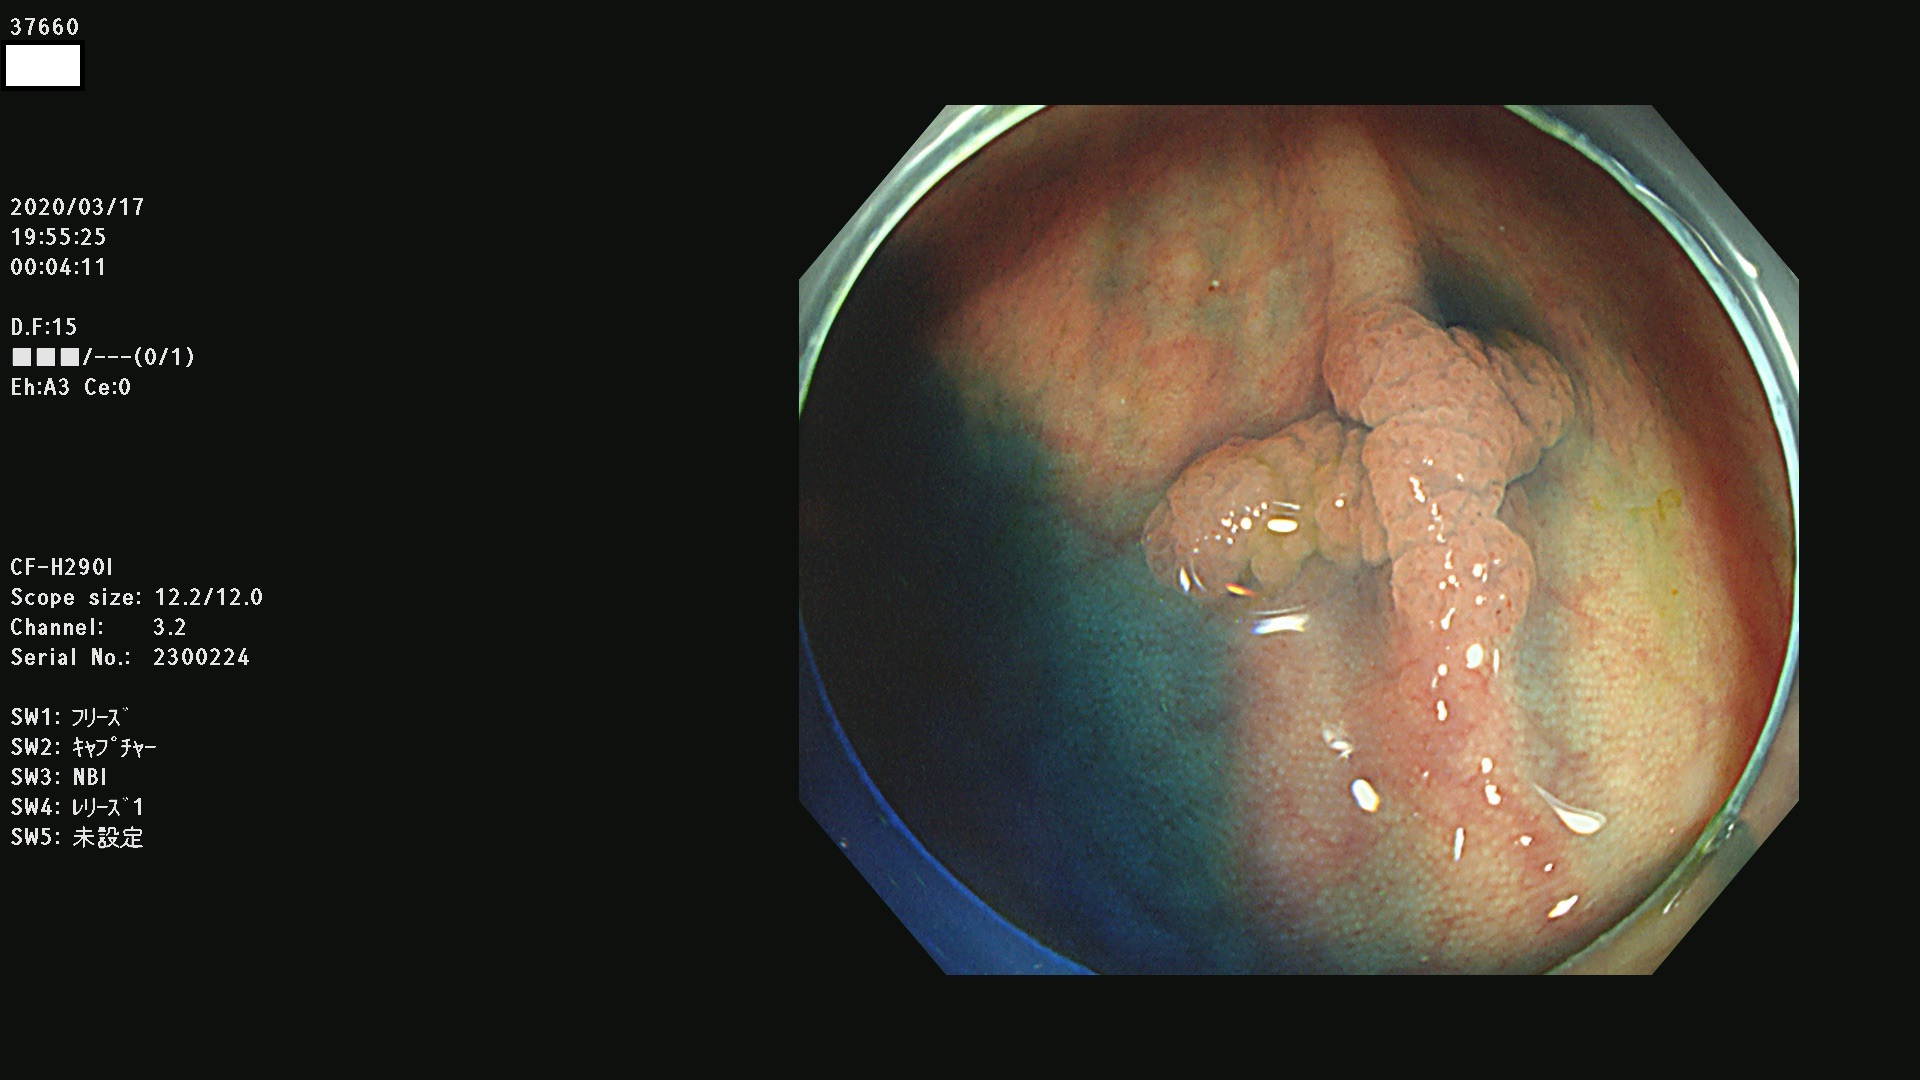

発見困難で危険性の高い平坦型病変(上記100名より抽出)